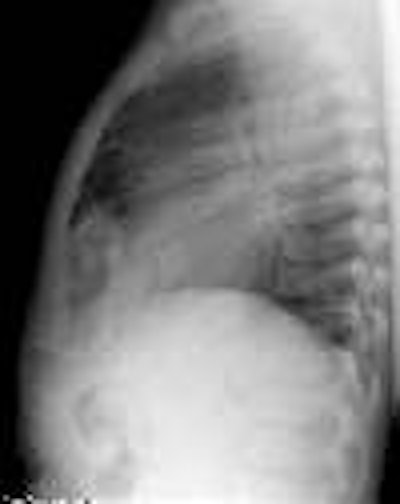

Morgagni Hernia:

The infant in the images below was referred for the evaluation of a "cystic anterior mediastinal mass." The "mass" was confirmed to be large bowel loops on a barium enema exam.

CXR: